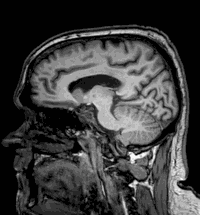

Jamie Brunt was diagnosed with a brain tumor after feeling extreme fatigue. (SWNS)

Jaime's brain scan. (SWNS)